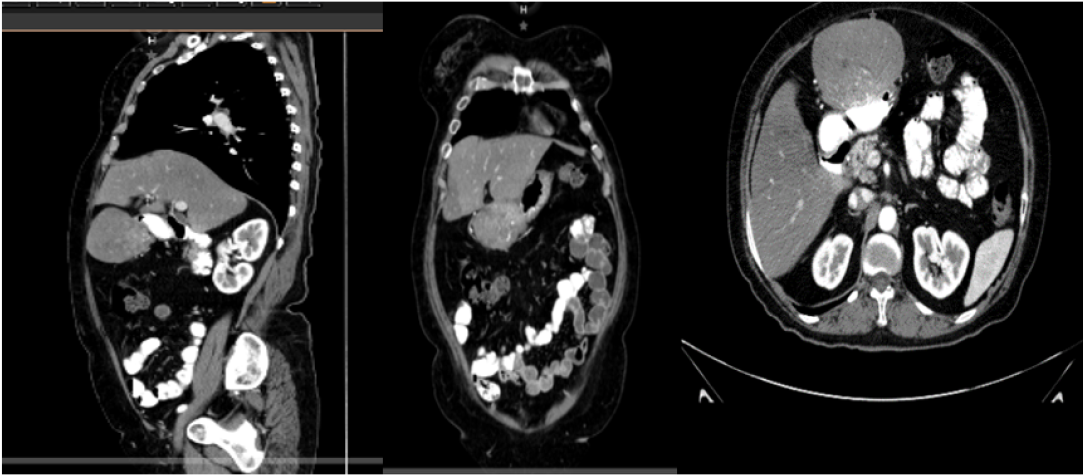

Prevalence of Thrombosis in the Splanchnic Territory Before and After the Appearance of Covid19